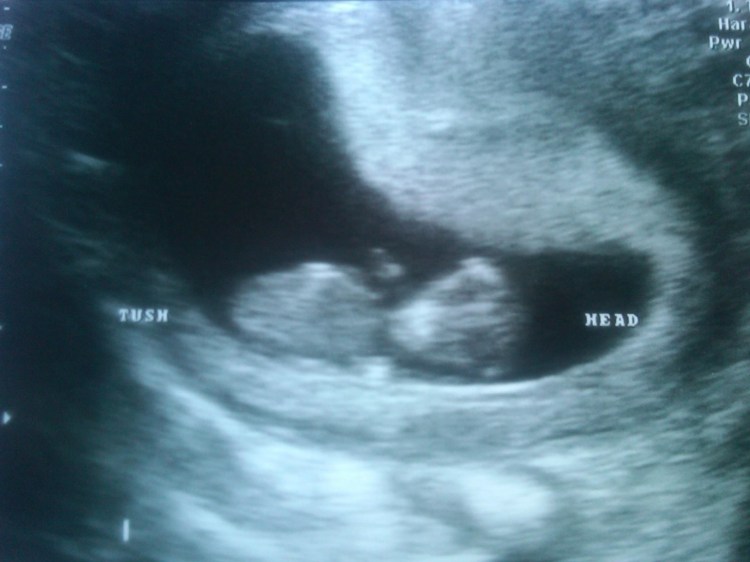

Today was our first ultrasound! Meet Baby Maute who has affectionately been named Maute Moo by my dear friend Kerrie. Maute Moo is due December 27th (oh baby – more on my feeling about a Christmas baby over the next few months). We are all beaming with excitement in our house. Cole was happier than I could have hoped. The grandparents are thrilled.

Now that we’ve had the ultrasound and we’ve seen the baby and heard the heartbeat, I feel much more comfortable sharing our baby news. While there will be lots of baby talk between now and the new year, I promise this isn’t going to become just a baby blog. The whole process is fun and crazy and exciting and nerve-racking. I plan on maintaining my running unless I have complications. I will also be doing a lot of yoga. Routine meals are balancing themselves back out, but I’m not responsible for the cravings!